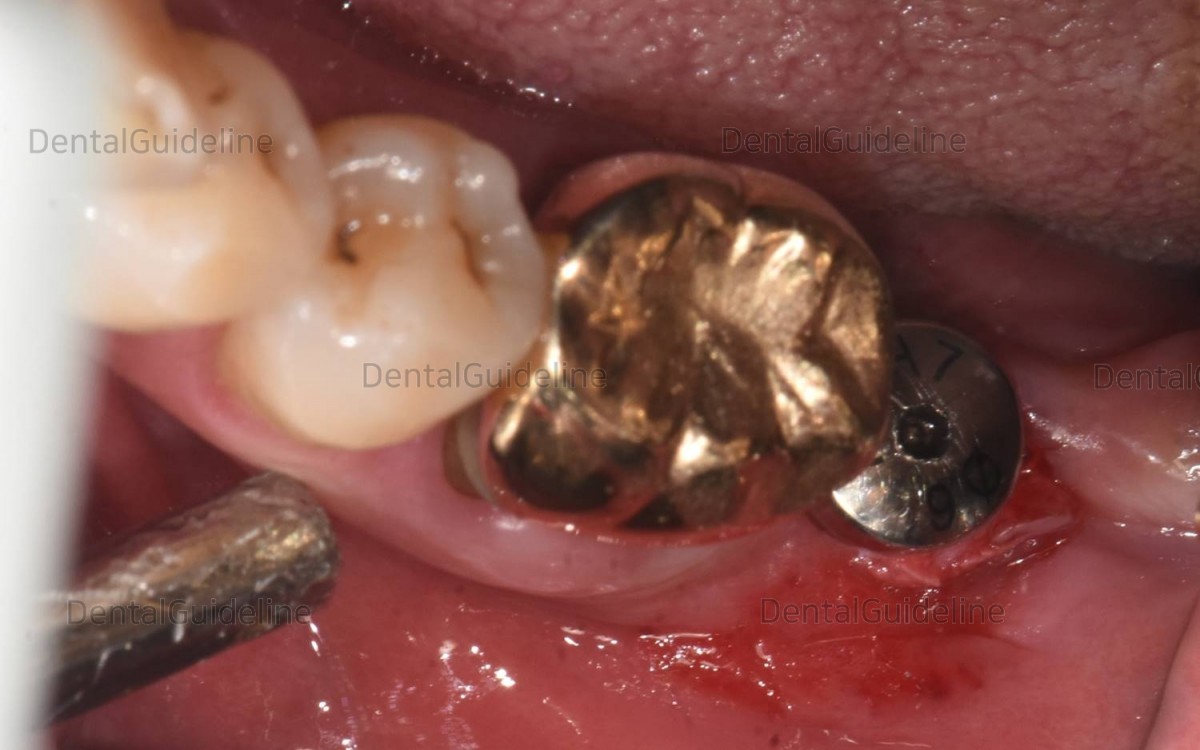

Intraoral photo before the surgery

Flapless

surgery was performed. An initial drill(Ø2.2mm) was

used for osteotomy with saline cooling at 800rpm followed by serial drillings

with non-irrigation at a speed of less than 100rpm.

(Arum Dentistry NB1 4.5/10mm)

A healing abutment was engaged to the

fixture trying to expand the gum.

A final-sized healing abutment was

engaged to the fixture.